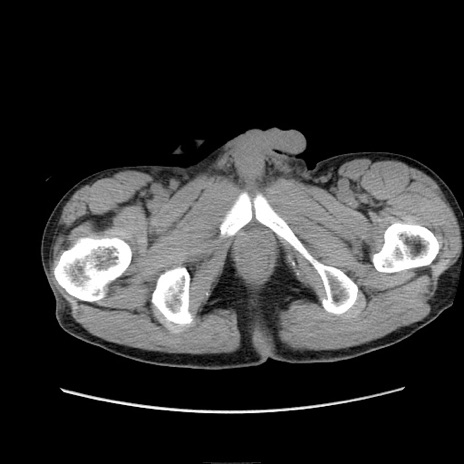

症例11(横断像)

【症例】 60歳代男性

【主訴】 下腹部痛

【現病歴】 本日夜中より下腹部痛の症状認め、受診。

【既往歴】 膀胱癌(膀胱全摘+尿管皮膚瘻術) 、胃癌術後

【身体所見】 BT 35.3℃、PR 58/min、BP 136/98mHg、腹部平坦、軟、腸蠕動音±、ストマ留置あり、左上腹部~正中部に圧痛あり、反跳痛なし。

【データ】WBC 5100、CRP0.01